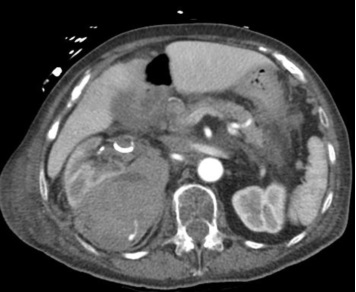

医源性肾创伤,移植肾活检后,动脉瘤

![]()

产后出血子宫动脉微Coil末端栓塞:导管头尽量接近出血点

直接栓塞/终末动脉栓塞/产后大出血栓塞

男,30,输尿管近端结石,体外碎石后,大量血尿